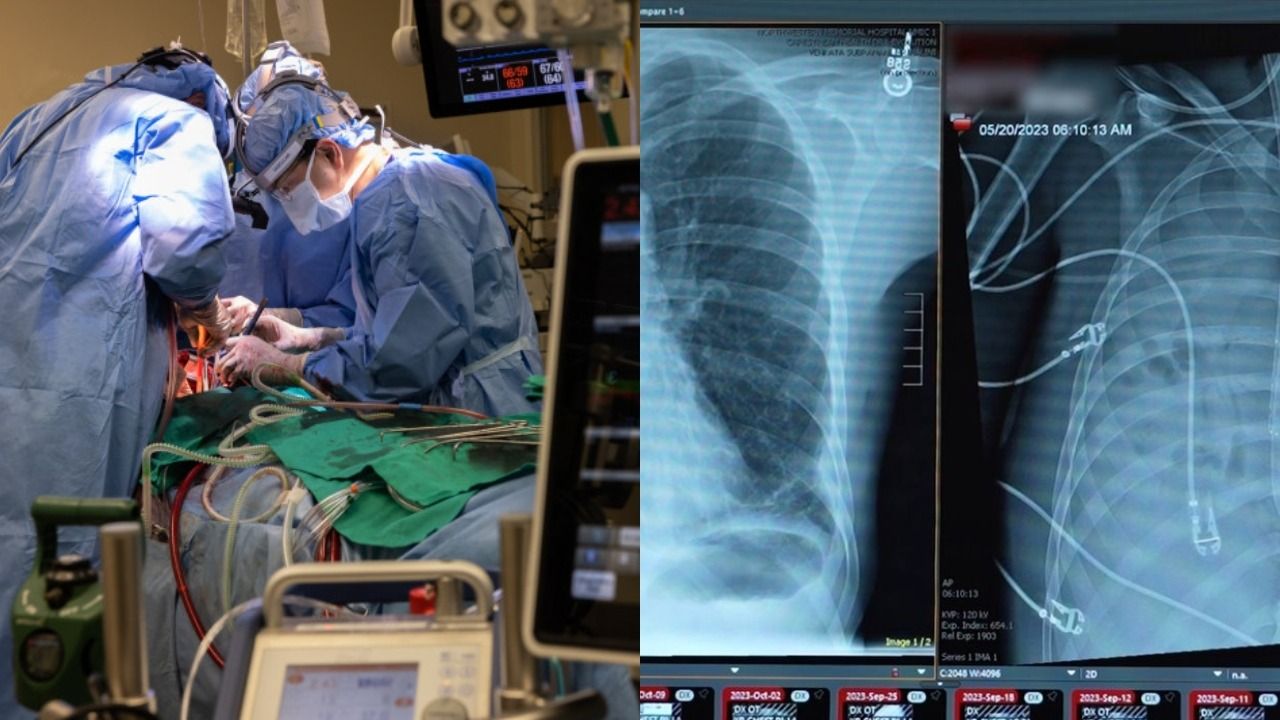

अमेरिका में डॉक्टरों ने एक ऐसा इलाज किया है जिसे आधुनिक चिकित्सा का बड़ा चमत्कार माना जा रहा है. 33 साल के एक युवक को इन्फ्लूएंजा और एक ड्रग-रेजिस्टेंट बैक्टीरियल संक्रमण के कारण गंभीर लंग फेलियर हो गया था. उसकी हालत इतनी नाजुक हो गई थी कि सामान्य इलाज से उसे बचाना संभव नहीं लग रहा था. ऐसे में डॉक्टरों ने एक ऐसा फैसला लिया जिसकी वजह से उस मरीज की जान बच गई.

युवक के दोनों फेफड़े पूरी तरह खराब हो चुके थे. वे शरीर को पर्याप्त ऑक्सीजन नहीं दे पा रहे थे. इससे उसके दिल, किडनी और ब्लड प्रेशर पर भी असर पड़ने लगा था. डॉक्टरों की टीम ने जांच के बाद तय किया कि संक्रमित फेफड़ों को हटाना ही एकमात्र रास्ता है. यह फैसला आसान नहीं था, क्योंकि बिना फेफड़ों के इंसान का जिंदा रहना लगभग असंभव माना जाता है.

डॉक्टरों ने युवक को एक खास तरह के कस्टम एक्सटर्नल आर्टिफिशियल लंग सिस्टम से जोड़ा. यह सिस्टम शरीर के बाहर लगाया गया था. इसका काम खून को ऑक्सीजन देना और दिल में सामान्य ब्लड फ्लो बनाए रखना था. मशीन ने वही काम किया जो आमतौर पर फेफड़े करते हैं. इससे शरीर के दूसरे अंगों को जरूरी ऑक्सीजन मिलती रही.

इस सिस्टम की मदद से युवक 48 घंटे तक बिना फेफड़ों के जिंदा रहा. यह समय डॉक्टरों के लिए भी बड़ी चुनौती से कम नहीं था, लगातार उसकी निगरानी की गई. इस दौरान उसके दिल की धड़कन, ब्लड प्रेशर और किडनी की स्थिति में सुधार देखा गया. शरीर धीरे-धीरे स्थिर होने लगा. यह संकेत था कि इलाज सही दिशा में जा रहा है.

इन 48 घंटों के बाद युवक को लंग ट्रांसप्लांट के लिए तैयार किया गया. डॉक्टरों ने नए फेफड़े लगाए और शरीर ने उन्हें स्वीकार करना शुरू कर दिया. यह पूरी प्रक्रिया मेडिकल साइंस के लिए एक बड़ी उपलब्धि मानी जा रही है. विशेषज्ञों का कहना है कि इस तकनीक से भविष्य में गंभीर लंग फेलियर के मरीजों को नई उम्मीद मिल सकती है.